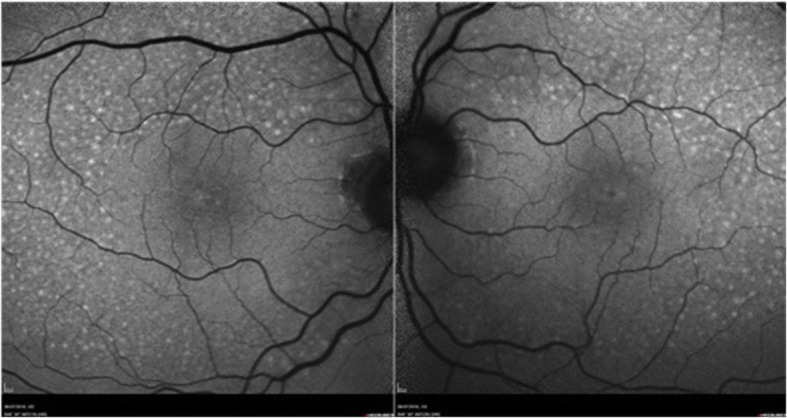

Fig. 4.

Autofluorescence image: Increased autofluorescence of scattered sub-retinal granular deposits in macular area